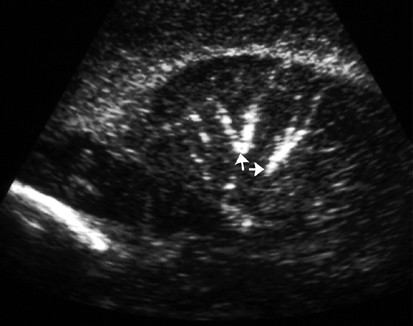

In the neonatal period, surviving children underwent a minimum of three HUS occurring in the first, second, and fourth weeks of life. These prospective studies were interpreted by two pediatric neurosonologists at the University of Chicago Children's Hospital (one of whom was DY). Papile grading of neonatal IVH,11 and diagnosis of PVL and LSV were made by consensus. Any infant deemed to have PVL by sonography also underwent magnetic resonance imaging. LSV was defined as the presence of bright, echogenic, linearly oriented vessels in the basal ganglia and thalamus. Follow-up developmental examinations were conducted at 4, 8, 12, and 18 corrected months of age.

Among 140 infants in the study for whom both LSV and IVH data were available, we diagnosed LSV in 10.0% (14 of 140). Neonatal IVH was found in 17.1% (24 of 140) of infants (Grade I, n=19; Grade II, n=0; Grade III, n=5; and Grade IV, n=0). Among the 14 babies who had LSV, 50% (seven of 14) also had neonatal IVH (Grade I, n=5; Grade III, n=2) (two-sided Fisher's exact test, p=0.002). One child was found to have PVL. (Figure 1 is the photograph of an HUS image from a baby in MagNET, who developed mineralizing vasculopathy. Figure 2 is a Doppler image showing that blood flow is not impeded through the striate vessels, thus the hyperechogenicity occurs in the walls of blood vessels and not in their lumina.) There were no statistically significant differences by univariate analysis in the maternal and demographic variables among babies who had LSV as compared to babies who did not (Table 1). None of the babies were found to have clinical evidence for congenital infections (rubella, CMV, or syphilis), although the presence of funisitis in some of these children (see below) could reflect the presence of an infectious or inflammatory condition. Only one baby with LSV had major congenital anomalies (esophageal atresia with a distal tracheo-esophageal fistula, ventricular septal defect, and 13 left ribs), and none of the babies with LSV had chromosomal abnormalities.

Color Doppler energy in sagittal imaging of the same baby. The thalamostriate vessels, although highly echogenic, are not occluded since blood flow is demonstrated. Yellow shading illustrates higher velocity, midstream flow in the central lumen, whereas the red shading represents the slower flow velocity at the periphery of the lumen (note arrows in northeast quadrant image).